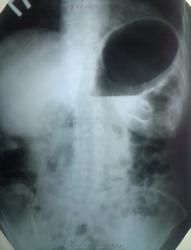

Женщина в возрасте 73 лет. Основная жалоба - отрыжка воздухом. Поступила по ургентности в хирургигическое отделение.Из анамнеза - отрыжка эта, в принципе, уже около года, возникла после стресса (смерть мужа), сейчас - ухудшение.

Произведена обзорная рентгенограмма брюшной полости.

После этого - ФГДС - ничего примечательного. На второй день - контрольная обзорная.